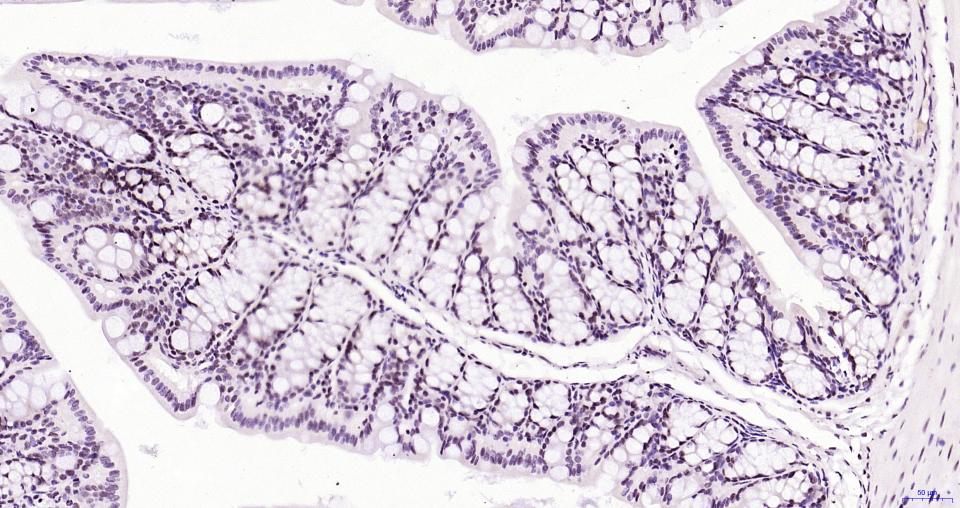

Paraformaldehyde-fixed, paraffin embedded Mouse Colon; Antigen retrieval by boiling in sodium citrate buffer (pH6.0) for 15 min; Antibody incubation with BRD4 Monoclonal Antibody, Unconjugated(bsm-61190R) at 1:200 overnight at 4°C, followed by conjugation to the bs-0295G-HRP and DAB (C-0010) staining.